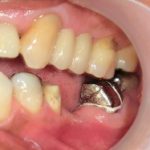

インプラントによる欠損の治療